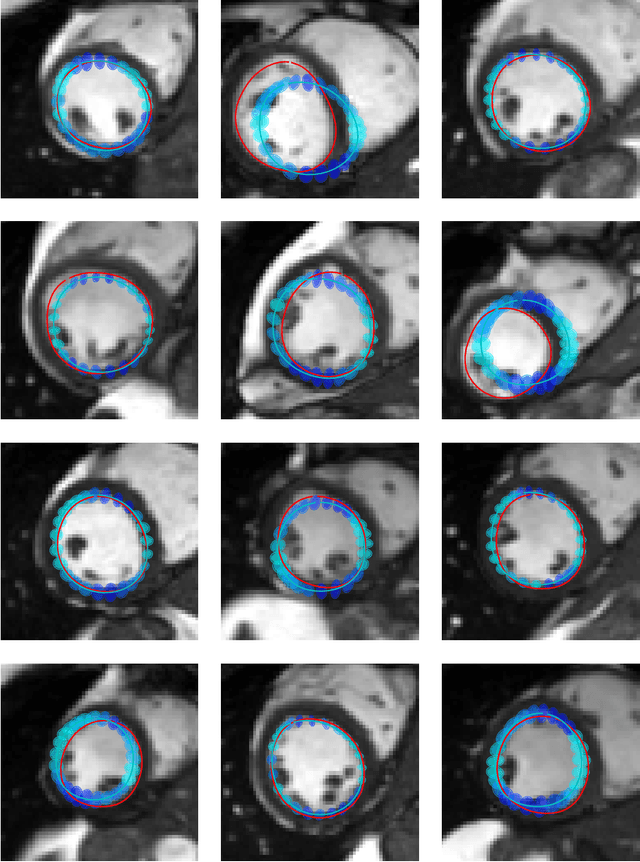

Abstract:Surface reconstruction is a vital tool in a wide range of areas of medical image analysis and clinical research. Despite the fact that many methods have proposed solutions to the reconstruction problem, most, due to their deterministic nature, do not directly address the issue of quantifying uncertainty associated with their predictions. We remedy this by proposing a novel probabilistic deep learning approach capable of simultaneous surface reconstruction and associated uncertainty prediction. The method incorporates prior shape information in the form of a principal component analysis (PCA) model. Experiments using the UK Biobank data show that our probabilistic approach outperforms an analogous deterministic PCA-based method in the task of 2D organ delineation and quantifies uncertainty by formulating distributions over predicted surface vertex positions.